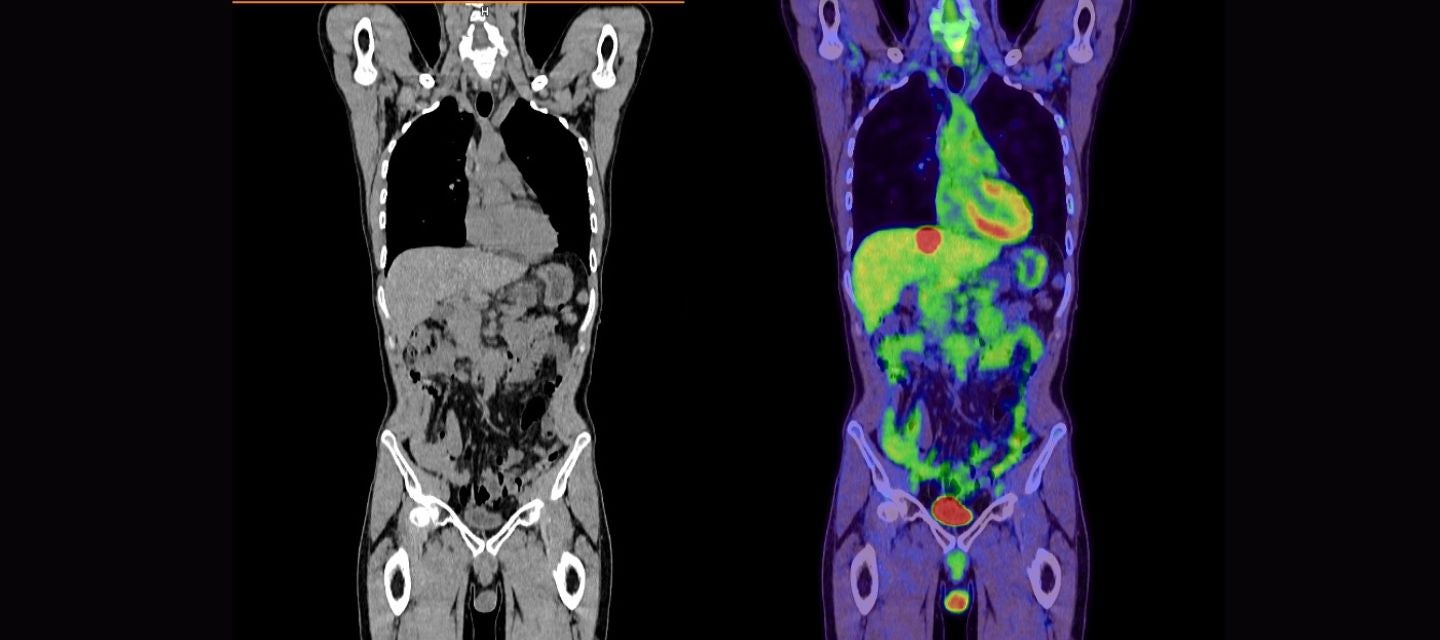

Mesane Kanseri PET CT

Mesane kanseri PET CT (Pozitron Emisyon Tomografisi ve Bilgisayarlı Tomografi), mesane kanserinin tanı, evreleme ve tedaviye olan yanıtını değerlendirmede kullanılan önemli bir görüntüleme tekniğidir. Bu yöntem, kanser hücrelerinin vücutta nasıl yayıldığını belirlemekte yardımcı olabilir ve tedavi planlaması için kritik bilgiler sağlar.

Mesane kanseri tanısı ve evrelemesinde PET/CT önemli bir rol oynar. PET/CT, vücuttaki metabolik aktiviteyi gösteren PET taraması ile anatomik ayrıntıları gösteren BT taramasının birleşimidir. Bu, doktorlara tümörün yerini, boyutunu, yayılımını ve metabolik aktivitesini değerlendirme olanağı sağlar.

PET-CT (Pozitron Emisyon Tomografisi ve Bilgisayarlı Tomografi), mesane kanseri gibi kanser türlerinin tanı, evreleme ve tedavi takibinde kullanılan güçlü bir görüntüleme yöntemidir. PET taraması, vücutta metabolik olarak aktif olan hücreleri tespit etmek için radyoaktif bir madde (genellikle florodeoksiglukoz – FDG) kullanırken, CT taraması ise vücudun iç yapılarının detaylı kesit görüntülerini sağlar. Bu iki teknolojinin birleştirilmesi, kanserin sadece anatomik değil, aynı zamanda fonksiyonel özelliklerini de ortaya koyarak tümörlerin vücudun diğer bölgelerine yayılıp yayılmadığını, metastaz yapıp yapmadığını daha net bir şekilde gösterebilir. Mesane kanserinin evrelemesi ve tedaviye yanıtın izlenmesi açısından PET-CT, özellikle ilerlemiş evrelerde ve nüks şüphesi olan hastalarda önemli bir tanı aracıdır.

Mesane kanserinin teşhis ve evrelemesinde PET-CT (pozitron emisyon tomografisi ve bilgisayarlı tomografi) önemli bir rol oynar. PET-CT, tümörlerin metabolik aktivitesini görselleştirmeye yardımcı olur ve kanserin vücuttaki yayılımını belirlemede etkin bir yöntemdir. Özellikle ileri evre mesane kanserlerinde, PET-CT, tümörlerin mesane dışındaki dokulara (örneğin, lenf bezleri, karaciğer veya akciğerler) yayılıp yayılmadığını tespit etmek için kullanılır. Ayrıca tedaviye yanıtı değerlendirmek ve hastalığın nüksünü erken dönemde saptamak için de faydalıdır. Ancak, PET-CT her zaman rutin olarak kullanılmaz; genellikle klinik olarak anlamlı bir yayılma şüphesi varsa veya daha hassas görüntüleme gerektiğinde tercih edilir.